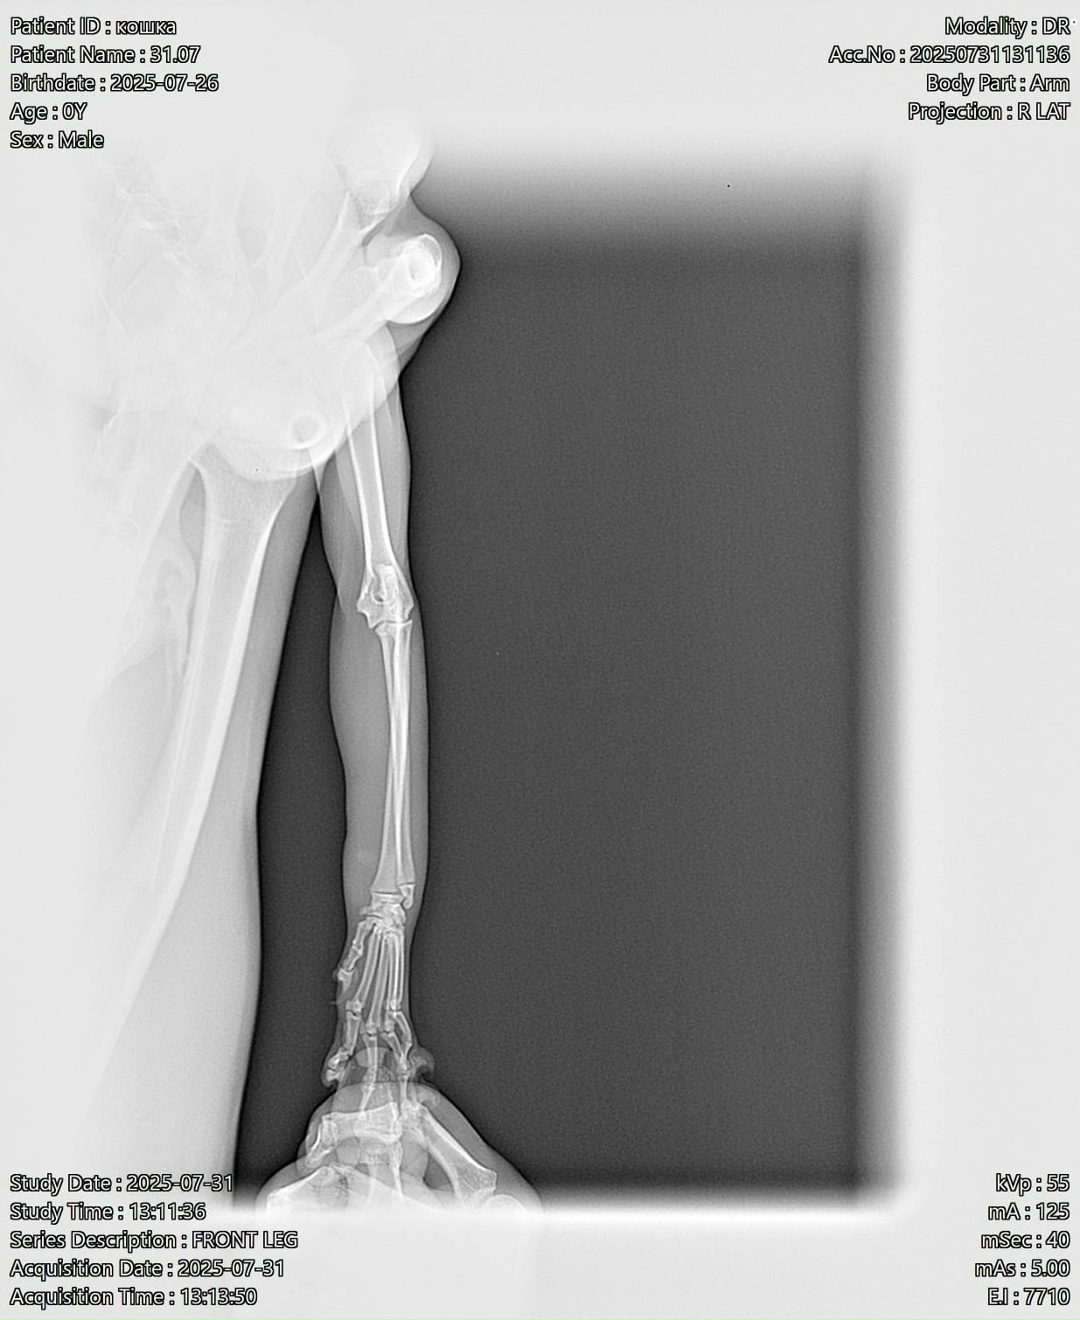

Только вот счастью нужна была помощь-передняя лапка кошки висела плетью, кошка на неё не наступала-очень похоже на перелом😢

И вот сегодня кошечку осмотрели ветеринары клиники Айболит г. Альметьевска.

Перелома нет, предположительно кошку кто-то укусил, лапка воспалилась, распухла и болит, поэтому кошка на неё не наступает.

Лечение назначено.